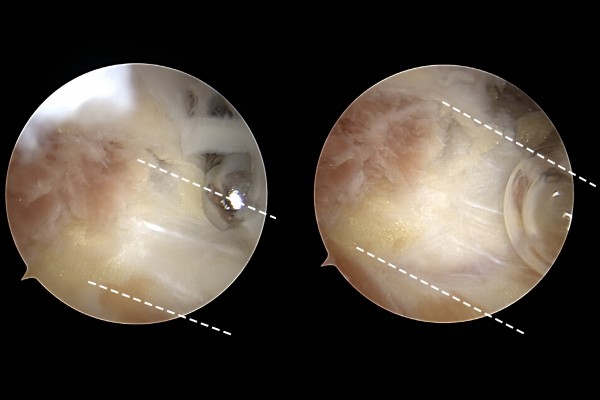

환자분의 발바닥 상태를 자세히 파악하기 위해서 MRI 검사를 진행하였고, MRI에서 까만 족저근막 주위에 하얀 염증이 확인되었고,

관절내시경 화면에서 족저근막이 확인됩니다.

족저근막을 수술도구를 이용하여 부분적으로 터서 늘려줍니다.